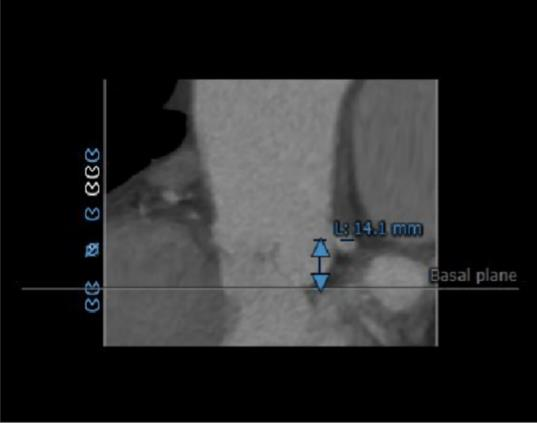

冠脉高度测量:

左冠开口高度14.1mm